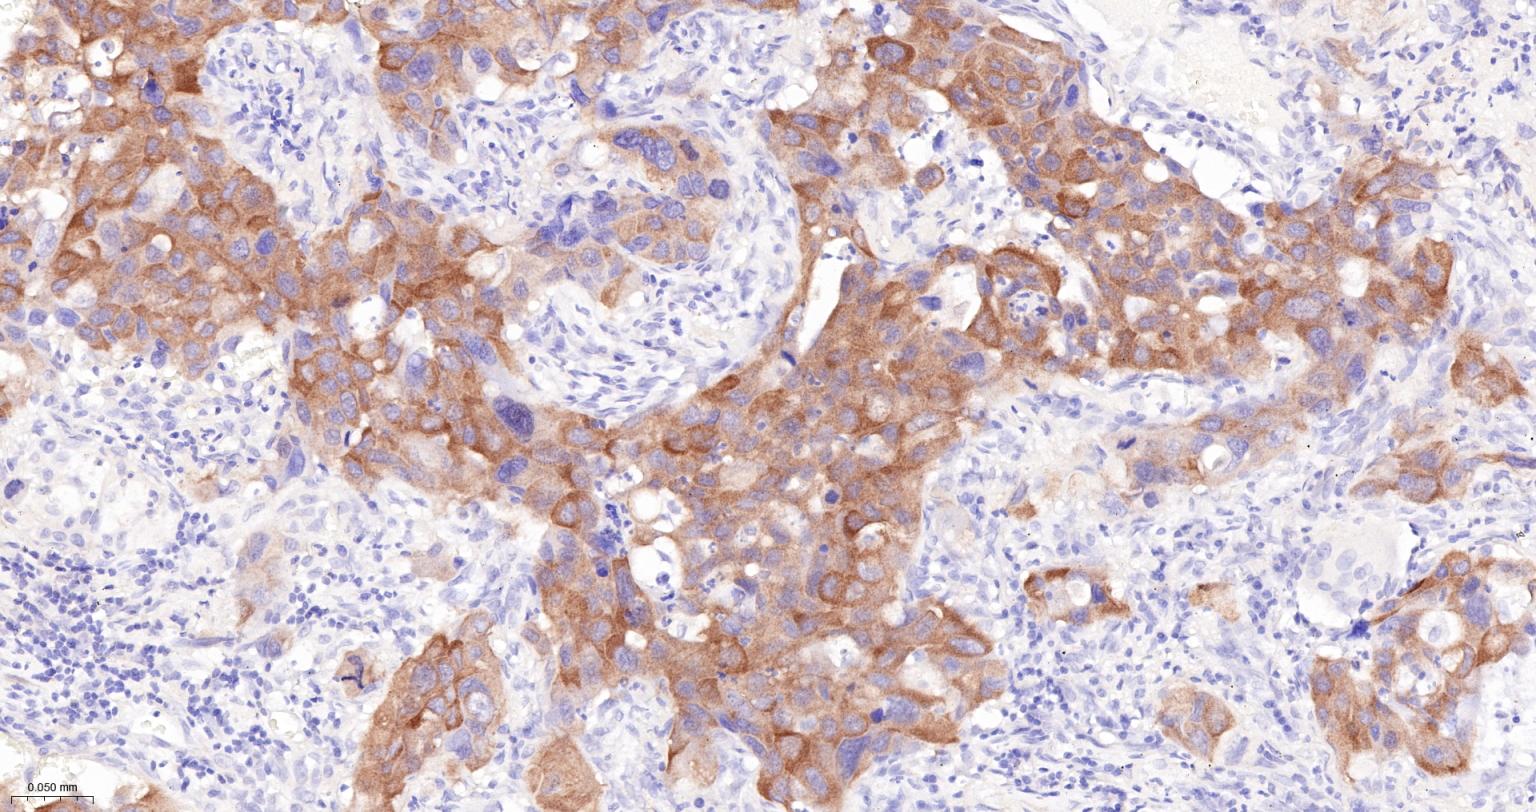

Paraformaldehyde-fixed, paraffin embedded Human Breast Cancer; Antigen retrieval by boiling in sodium citrate buffer (pH6.0) for 15 min; The section was incubated with INPP4B Monoclonal Antibody, Unconjugated (bsm-61303R) at 1:200 overnight at 4°C, followed by conjugation to the bs-0295G-HRP and DAB (C-0010) staining.